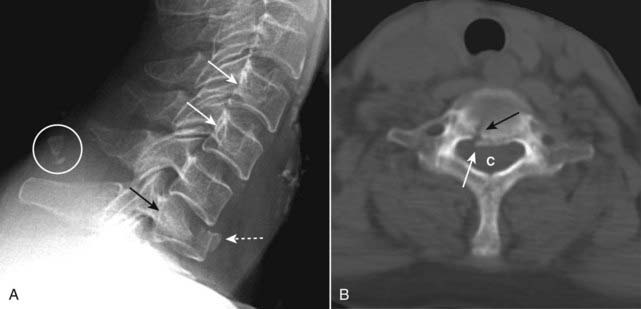

image They are best evaluated on the lateral view of the cervical spine on conventional radiography and the sagittal view on CT.

imageThe fracture effectively separates the posterior aspect of the C2 vertebral body from the anterior aspect of C2 allowing the anterior aspect of C2 to sublux forward on the body of C3 (Fig. 24-19).

Figure 24-19 Hangman’s fracture.

A hangman’s fracture results from a hyperextension-compression injury. It involves fractures through the posterior elements of C2 best evaluated on the lateral view. The fracture (dotted white arrow shows fracture line) effectively separates the posterior aspect of the C2 vertebral body from the anterior aspect of C2 allowing the anterior aspect to sublux forward on the body of C3. Notice that the spinolaminar line of C2 lies posterior to the other vertebral bodies (solid black arrow) and the anterior aspect of C2 lies forward of the anterior body of C3 (solid white arrow).

Some hangman fractures are less displaced, so that CT may be needed for their detection.

image Because hangman fractures lead to overall widening of the bony canal, they are usually not associated with neurologic deficits. This is in contradistinction to the injury after which this fracture is named, the fracture incurred during a judicial hanging in which there was hyperextension leading to a fracture of C2 and marked distraction of C2 from C3 associated with distraction of the spinal cord itself.

imageFindings of burst fractures include a comminuted, compression fracture of the vertebral body in which the posterior aspect of the body is bowed backward toward the spinal canal. CT is the best imaging modality for identifying bony fragments in the spinal canal (Fig. 24-20).

Figure 24-20 Burst fracture, radiograph, and CT.

A, Findings include a comminuted, compression fracture of the vertebral body in which the anterior vertebral body is displaced forward (dotted white arrow) while the posterior aspect of the body is propelled dorsally toward the spinal canal (solid black arrow). Notice how the posterior aspects of vertebral bodies are normally concave inward (solid white arrows). Calcification of the ligamentum nuchae is of no clinical consequence (white circle). B, Axial CT scan of the spine shows a fracture of the body (solid black arrow) and the retropulsed fragment (solid white arrow) protruding into the spinal canal (C).